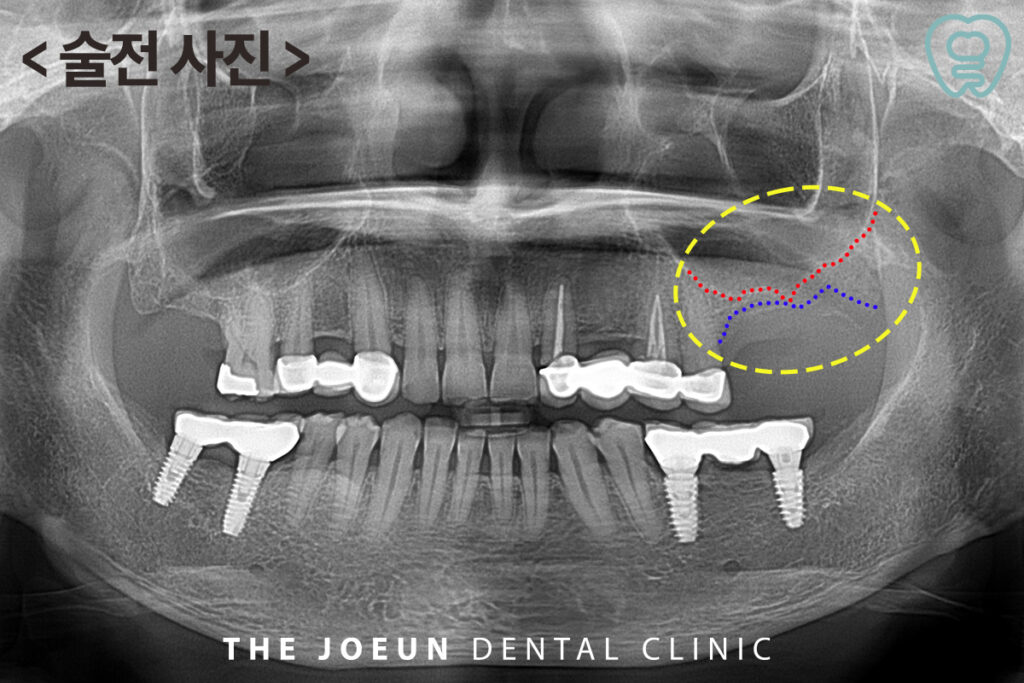

환.자분께서는 왼쪽 위 어금니 부위가 상실되신지 오래되어 치료 상.담을 위해 내원해 주셨는데요. 파노라마 촬영 결과, 치아를 상실하신 지 오래되어 잇몸뼈가 거의 상악동과 겹쳐 보일 정도로 많이 흡수되어 있는 상태였습니다.

빨간색 점선으로 표시된 부분이 공기주머니인 상악동을 표시한 것이며, 아래쪽 노란색 점선 부분이 남아 있는 잇몸뼈를 표시한 것인데요. 임플란트를 식립하기 위한 공간이 부족하였기 때문에 상악동을 들어 올려 뼈이식을 동반한 임플란트 식립을 계획하였습니다.